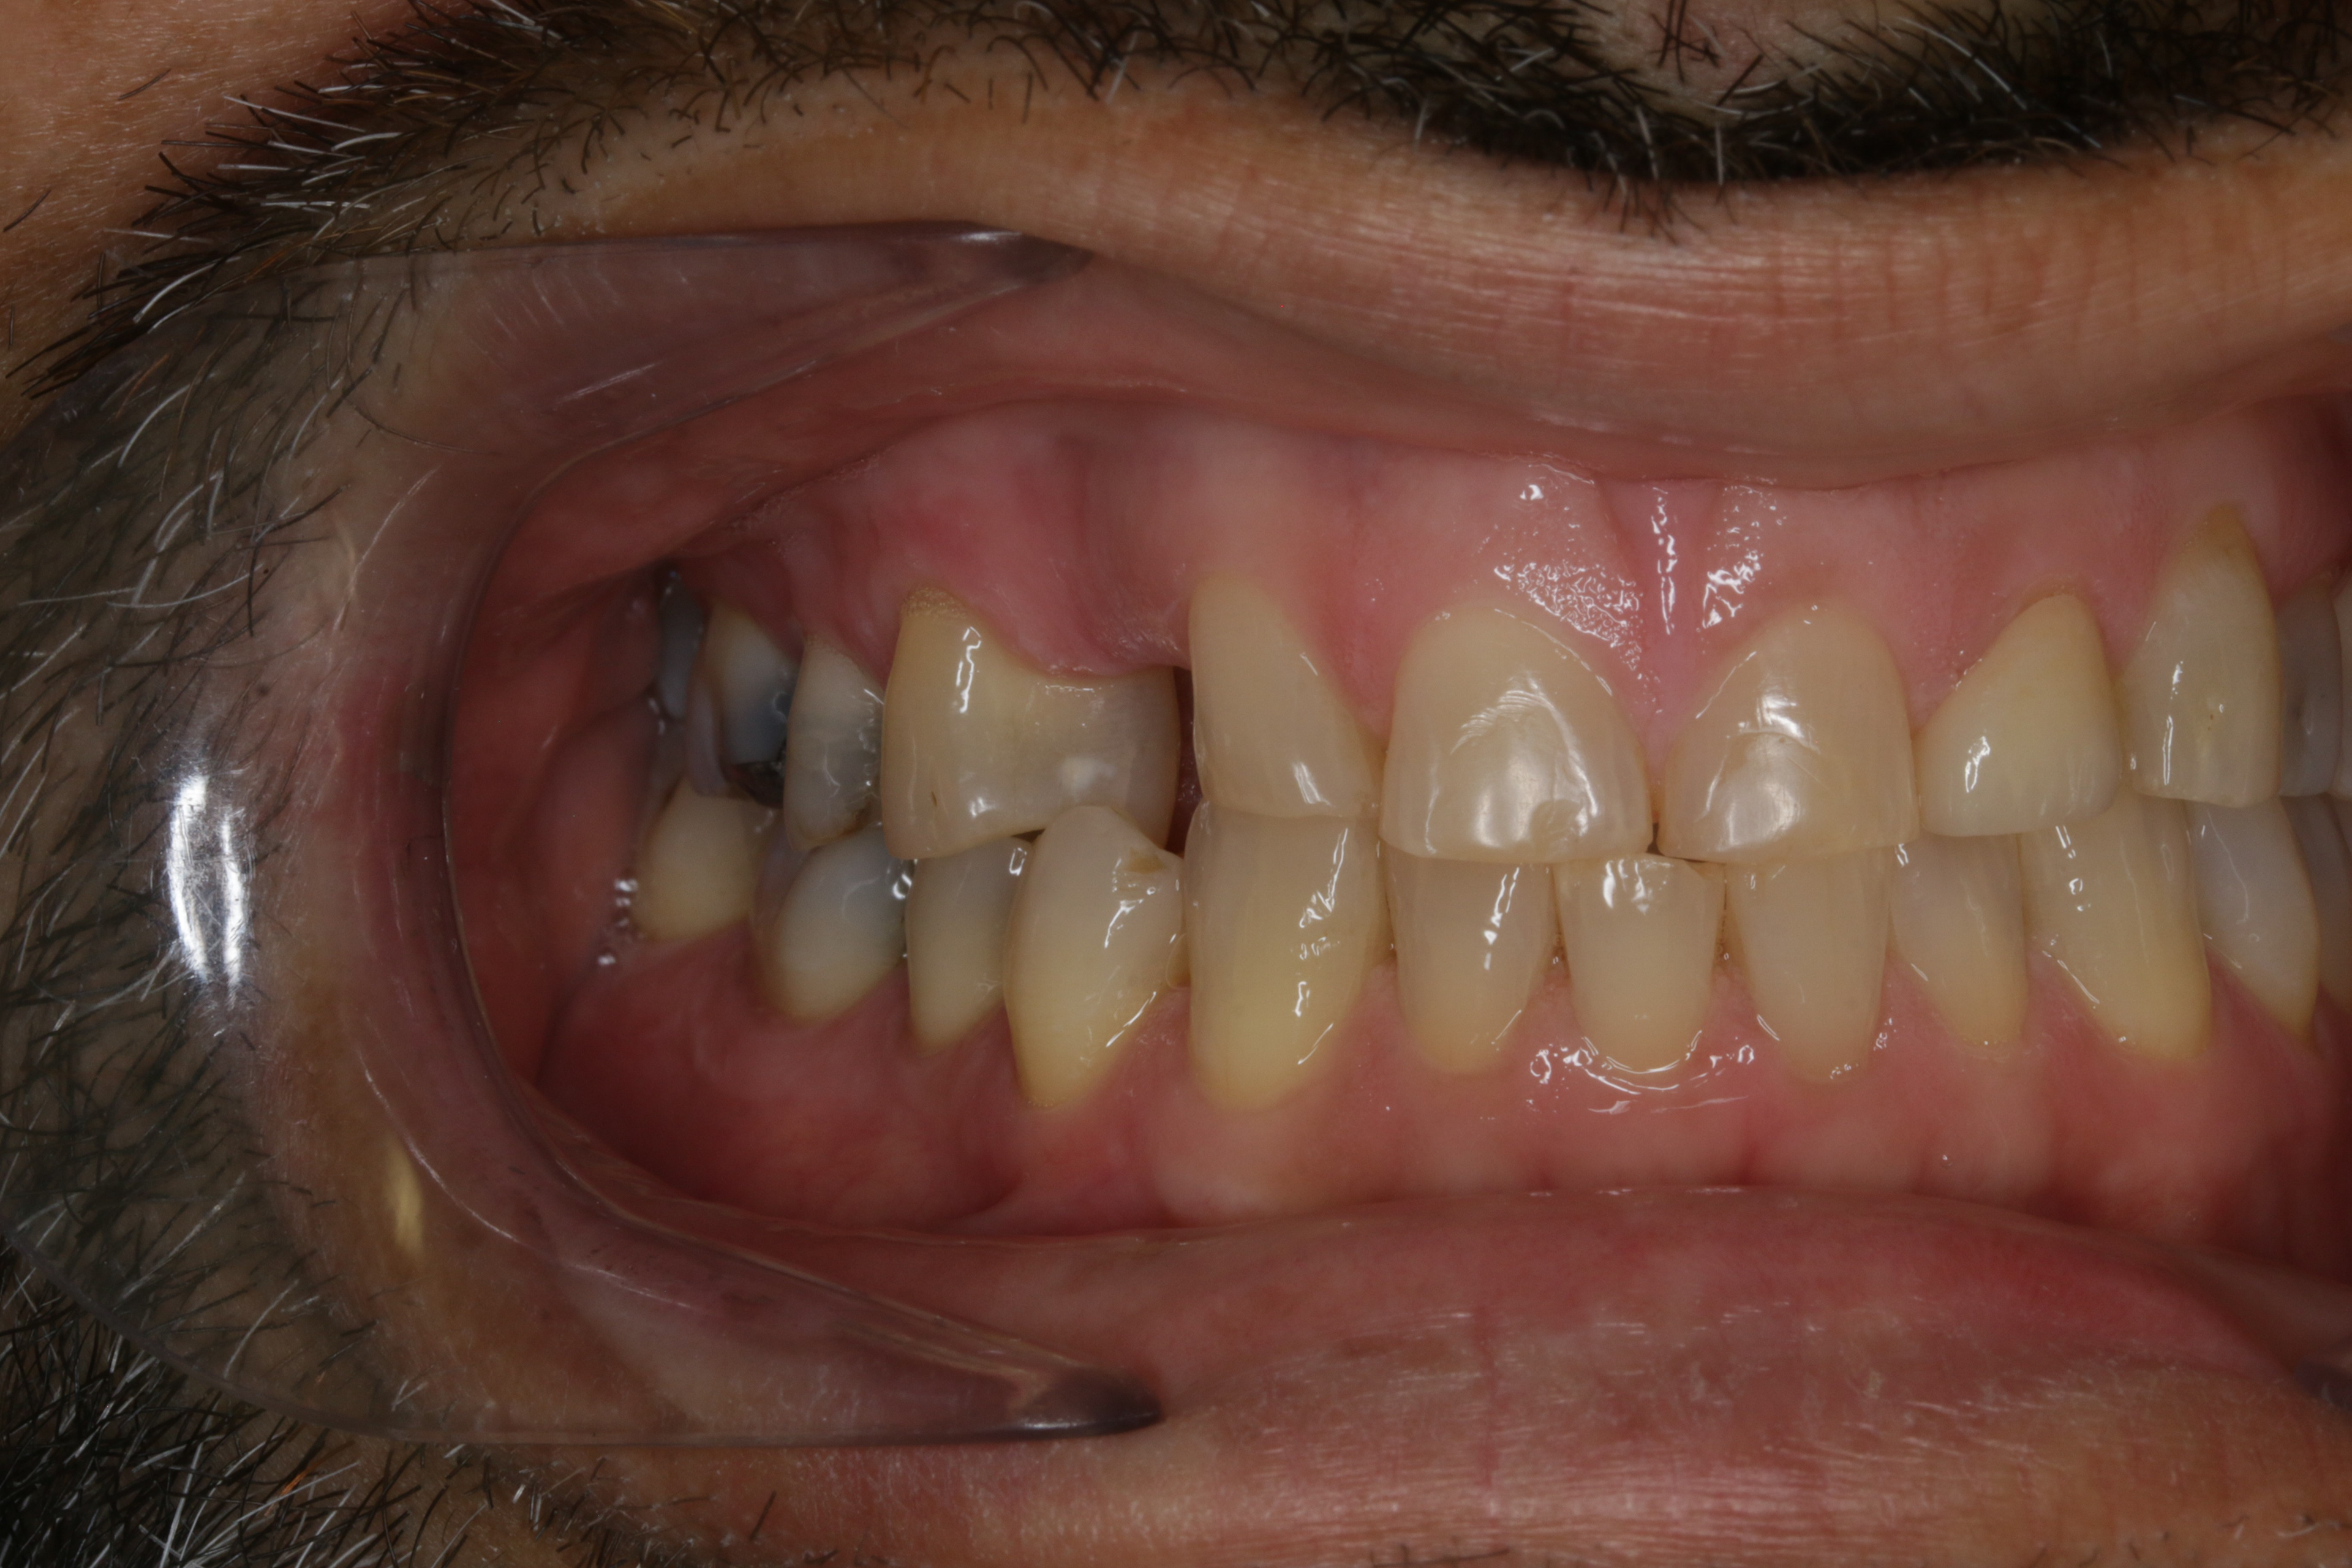

INITIAL RECORDS

BEFORE